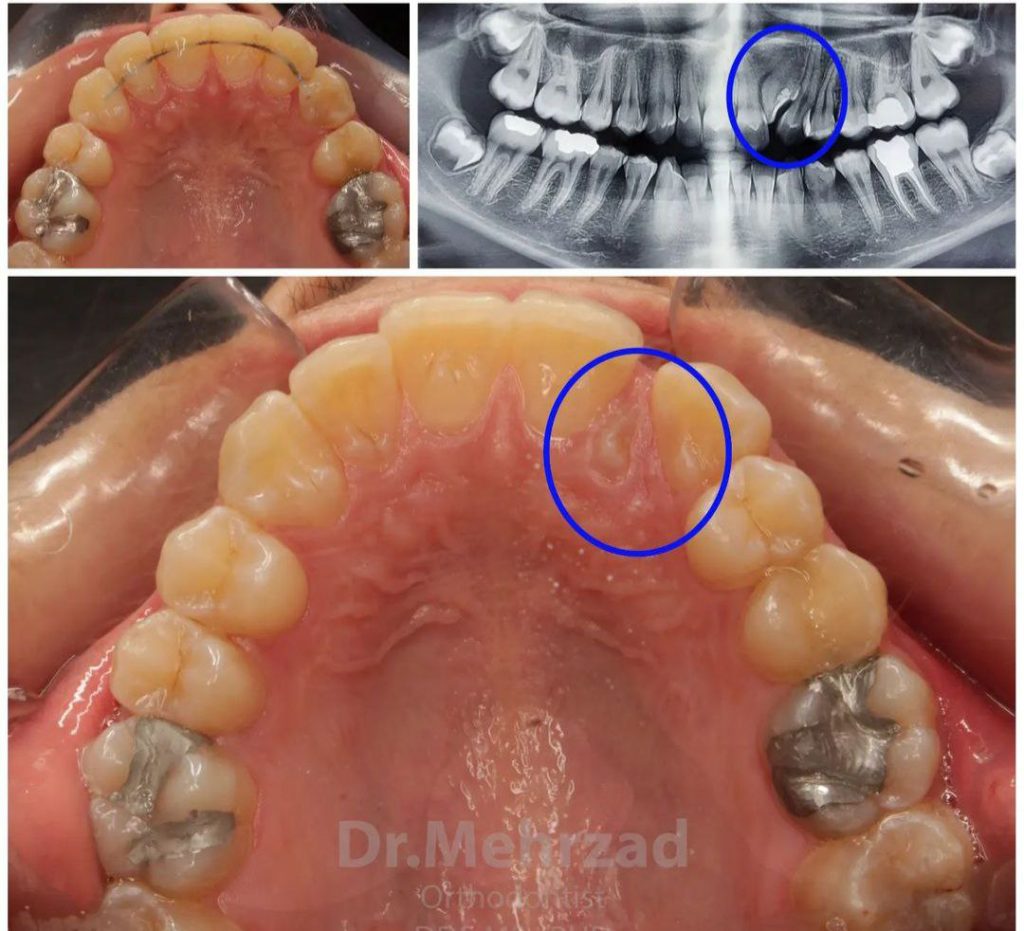

مشکلات فکی

در صورتی که فک بالا و پایین به درستی با هم تطابق نداشته باشند و به مشکلاتی مانند باز بودن یا بسته بودن ناقص دهان منجر شوند، ارتودنسی می تواند به اصلاح وضعیت فک کمک کند.

دندان های پیش آمده یا عقب رفته

اگر دندان های جلو یا عقب شما بیش از حد بیرون زده یا عقب رفته باشند، این مشکلات می توانند منجر به آسیب پذیری دندان ها و مشکلات جویدن شوند.